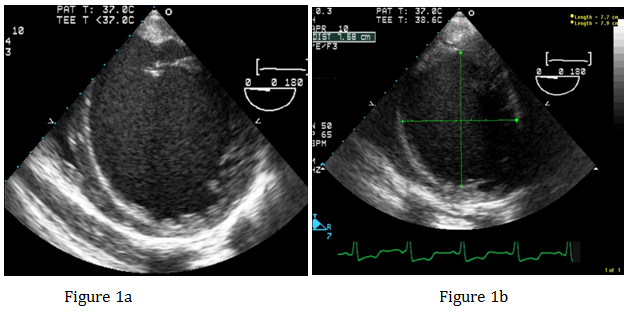

After emptying the stomach, the TEE probe was placed without difficulty. IABP was placed via the right femoral artery. Position of the IABP was confirmed with the TEE. Operation of the IABP was confirmed. A left femoral venous cordis was placed and central access was established. Preoperative TEE found an LV ejection fraction of approximately 5%, severely dilated LV (Figure 1a & Figure 1b), moderately dilated right ventricle, and moderate to severe right ventricular hypokinesis. Patient had a 4+ MR, with significant reversal of the systolic component of the right superior pulmonary venous profile (Figures 1c & Figure 1d).

Figure 1a&1b Transgarstric Short Axis view of the left ventricle showing severely dilated left ventricle.